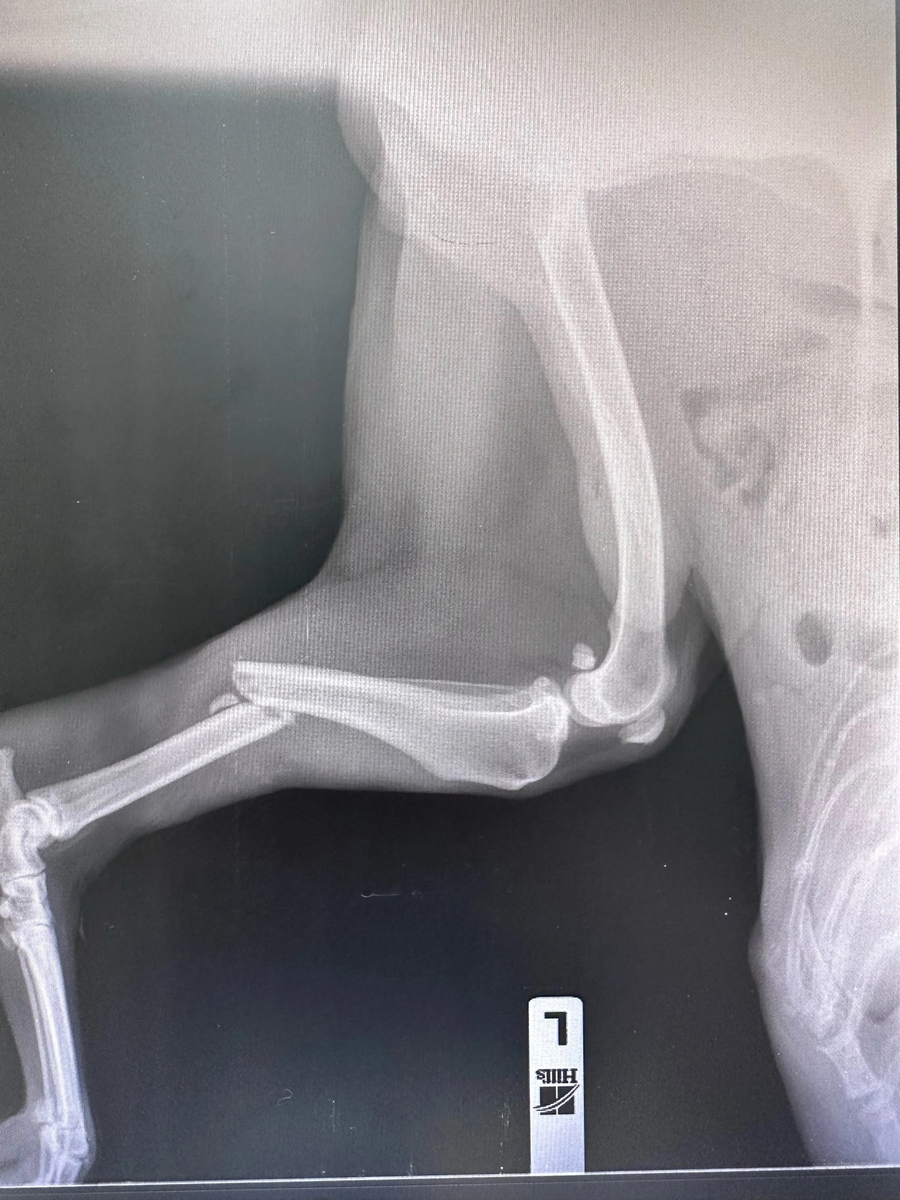

Операция прошла успешно, сломанная конечность была сломана и Снежок (так назвали этого дедушку) хорошо вышел из наркоза! Сейчас Снежок на домашней передержке, схомячил порцию мяса и через короткое время вовсе расслабился, начал облизывать руки человека. Что может быть сильнее мысли, что мы с вами смогли помочь собаке, которая уже не ждала ничего хорошего? Это волшебно! Спасибо каждому за помощь, за быстрое реагирование и, конечно, внимание 💙

Операция прошла успешно, сломанная конечность была сломана и Снежок (так назвали этого дедушку) хорошо вышел из наркоза!